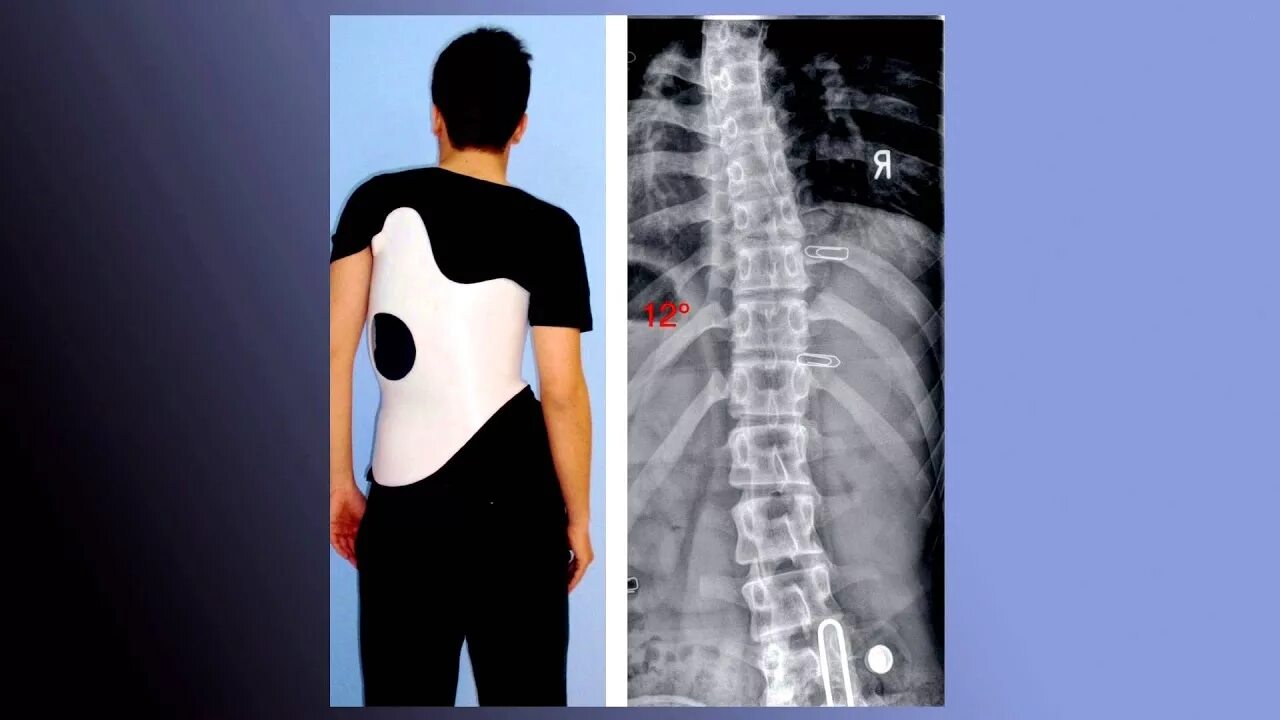

Сколиоз 4 степени у взрослых